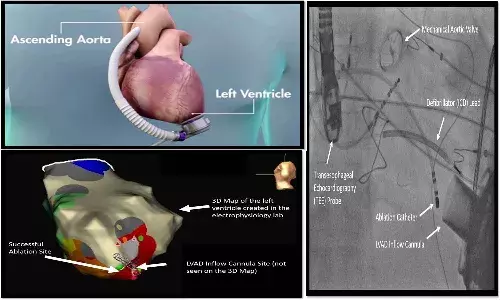

తీవ్ర హృద్రోగంతో బాధపడుతున్న యువకునికి కృత్రిమ గుండె సహాయంతో విజయవంతమైన చికిత్స

Serious Heart Disorder Treatment. హృదయస్పందన క్రమపద్ధతిలో లేక తివ్ర హృద్రోగంతో బాధపడుతుండడం వల్ల లెఫ్ట్ వెంట్రిక్యులర్ అసిస్ట్ డివైస్ ద్వారా